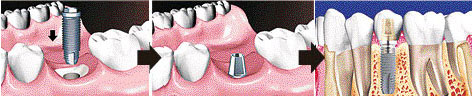

임플란트는 임플란트를 식립하고 그 위에 최종 보철물 (보통 크라운이라고 하죠)이 연결되어 치아가 만들어 집니다

‘따라서 임플란트와 보철을 함께 전공하신 원장님께서 시술하시는 것이 가장 바람직합니다

임플란트와 보철을 둘 다 전공하신 원장님께 임플란트 수술을 받는것이 가장 바람직합니다